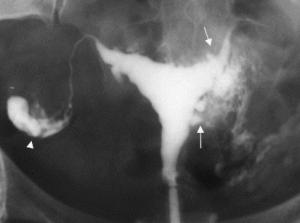

Dans l'endométriose, du tissu semblable au tissu endométrial se développe, hors de l'utérus, entrainant lésions et kystes ou endométriomes. Le diagnostic, par échographie, radio ou IRM le plus souvent, est généralement trop tardif. Une femme sur dix à une femme sur vingt aura ainsi des dommages aux ovaires, à la vessie ou au rectum : La maladie touche en effet entre 10 et 15% des femmes fécondes et 20 à 50% des femmes infertiles.Le traitement de l'endométriose peut être médical ou chirurgical.